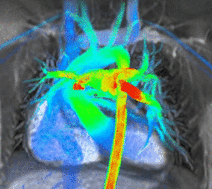

Blood flow can be visualized and quantified on scans acquired with a scan sequence called 4D flow. These volumetric scans capture multidirectional flow values anywhere within the imaged volume throughout the cardiac cycle, leading to a comprehensive exam of the entire anatomy.[15] Visualization can display flow velocity maps, vectors and streamline

4D flow visualization. flow (left) and streamlines (center) and vectors (right).